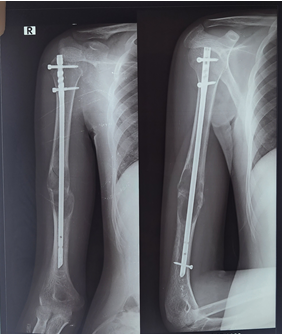

Figure 3: Immediate post op

Figure 4: xray at 2 months post op

Figure 5: Xray at 9 months post op

Figure 6: Xray at 11 month post op

Given the somewhat aggressive radiological features of the lesion and pathological fracture, the patient underwent surgical management in the form of closed intramedullary nailing of humerus and histopathological examination of the aspirate obtained on reaming of the medullary canal.

Postoperative period was uneventful and the lytic lesion gradually resolved over subsequent months and the fracture united. The patient achieved full range of movements at the shoulder and elbow and has resumed his routine activities after 8 months of surgery.

Serial imaging during every follow up showed progressive healing of the fracture site and regression of the cystic lesion. At 12 months post-surgery the recovery is satisfactory without evidence of any recurrence or complications.

During the placement of the intramedullary nail the undisplaced fracture got slightly displaced increasing our apprehensions regarding consolidation at the lesion and spontaneous union of the fracture.

However improved radiological picture depicting increased mineralisation at fracture site and signs of union at 2 months post-surgery laid our worries to rest.